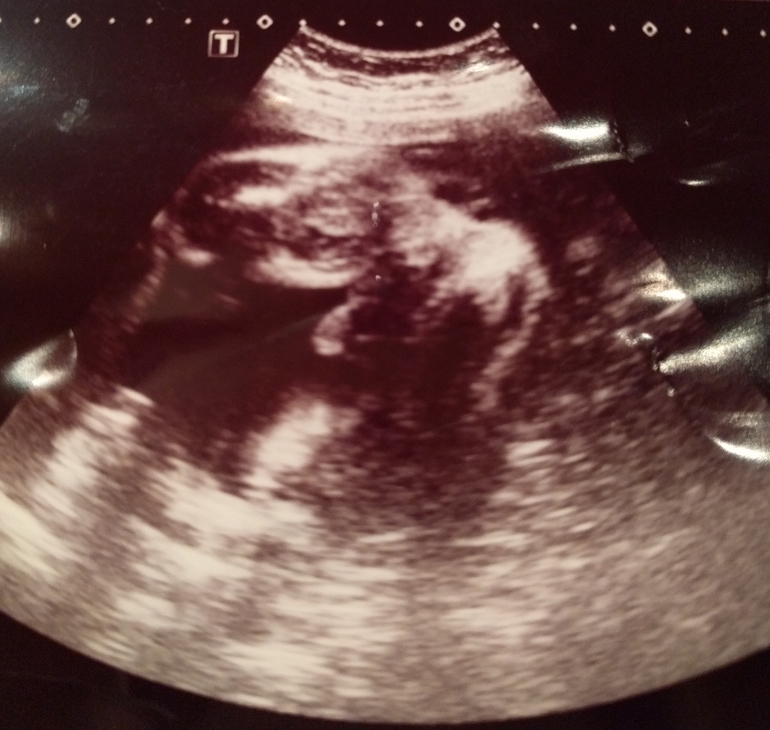

Да, мальчик. У дочи на таком сроке отчётливо было видно, что там половые губы и ничего не торчит.

Вот как у нас было видно.